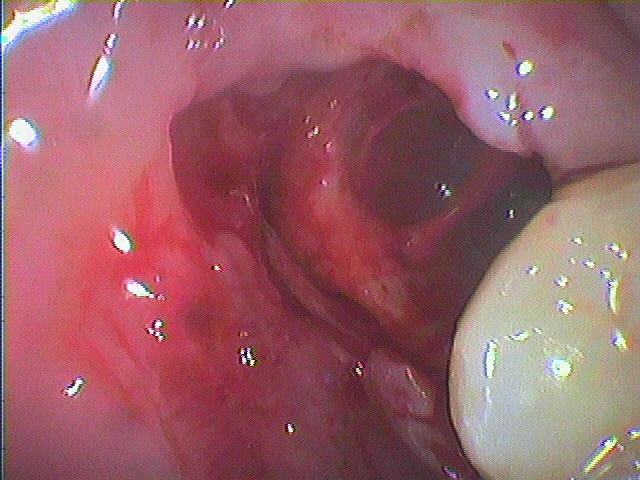

膿が出てくるフィステルが形成

数日後、症状がやんで抜歯の際には麻酔をかけると中から膿が出てきます